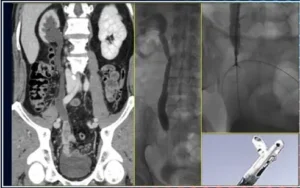

Un altro esempio è rappresentato dalla biopsia endoureterale, che può essere eseguita:

- per via ascendente, dalla uretra, in vescica e quindi nell’uretere

Biopsia endoureterale